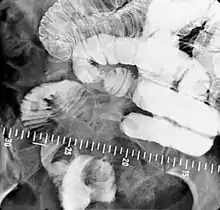

Barium meal examination showing the stomach and duodenum in double contrast technique with CO2 as negative contrast medium